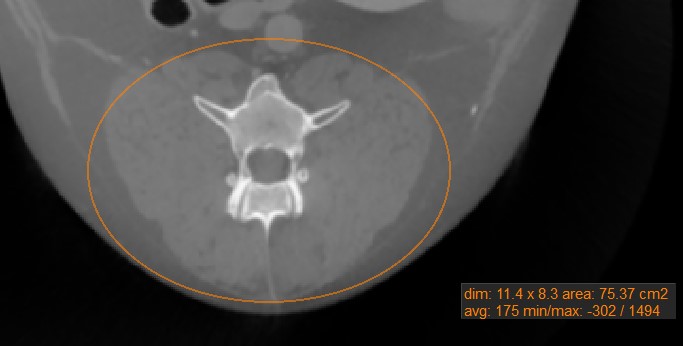

Ovalis mérés¶

Válassza ki a Ovalis mérés eszközt, és rendelje hozzá az elérhető egérgombok egyikéhez. Indítsa el a mérést az aktív kép szeletén való kattintással, majd húzza az egeret az ovális alak eléréséhez. Engedje el az egeret, ha elégedett a kijelölt terület méretével.

Az összes elérhető mérési érték megjelenik a mérés mellett.

A kijelölt terület módosításához mozgassa a négy pont egyikét, amely az ovális alak körüli téglalapot leírja, a Alapértelmezett eszközzel.